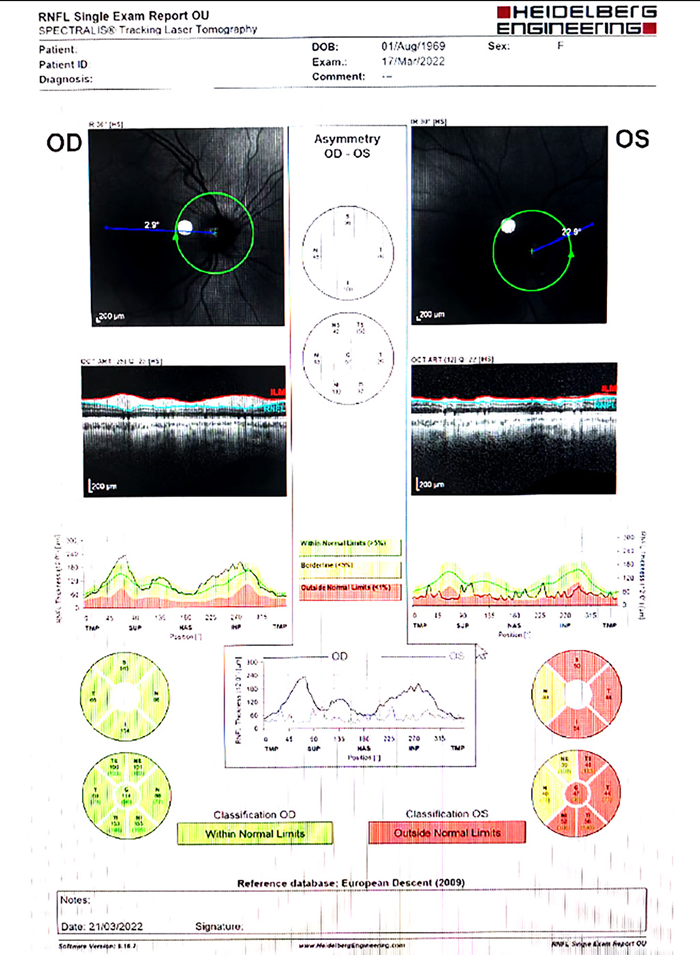

Figura 3. Segundo OCT CFN donde se evidencia empeoramiento.

Figura 4. CVC 24.2 donde se evidencia empeoramiento respecto del primero.